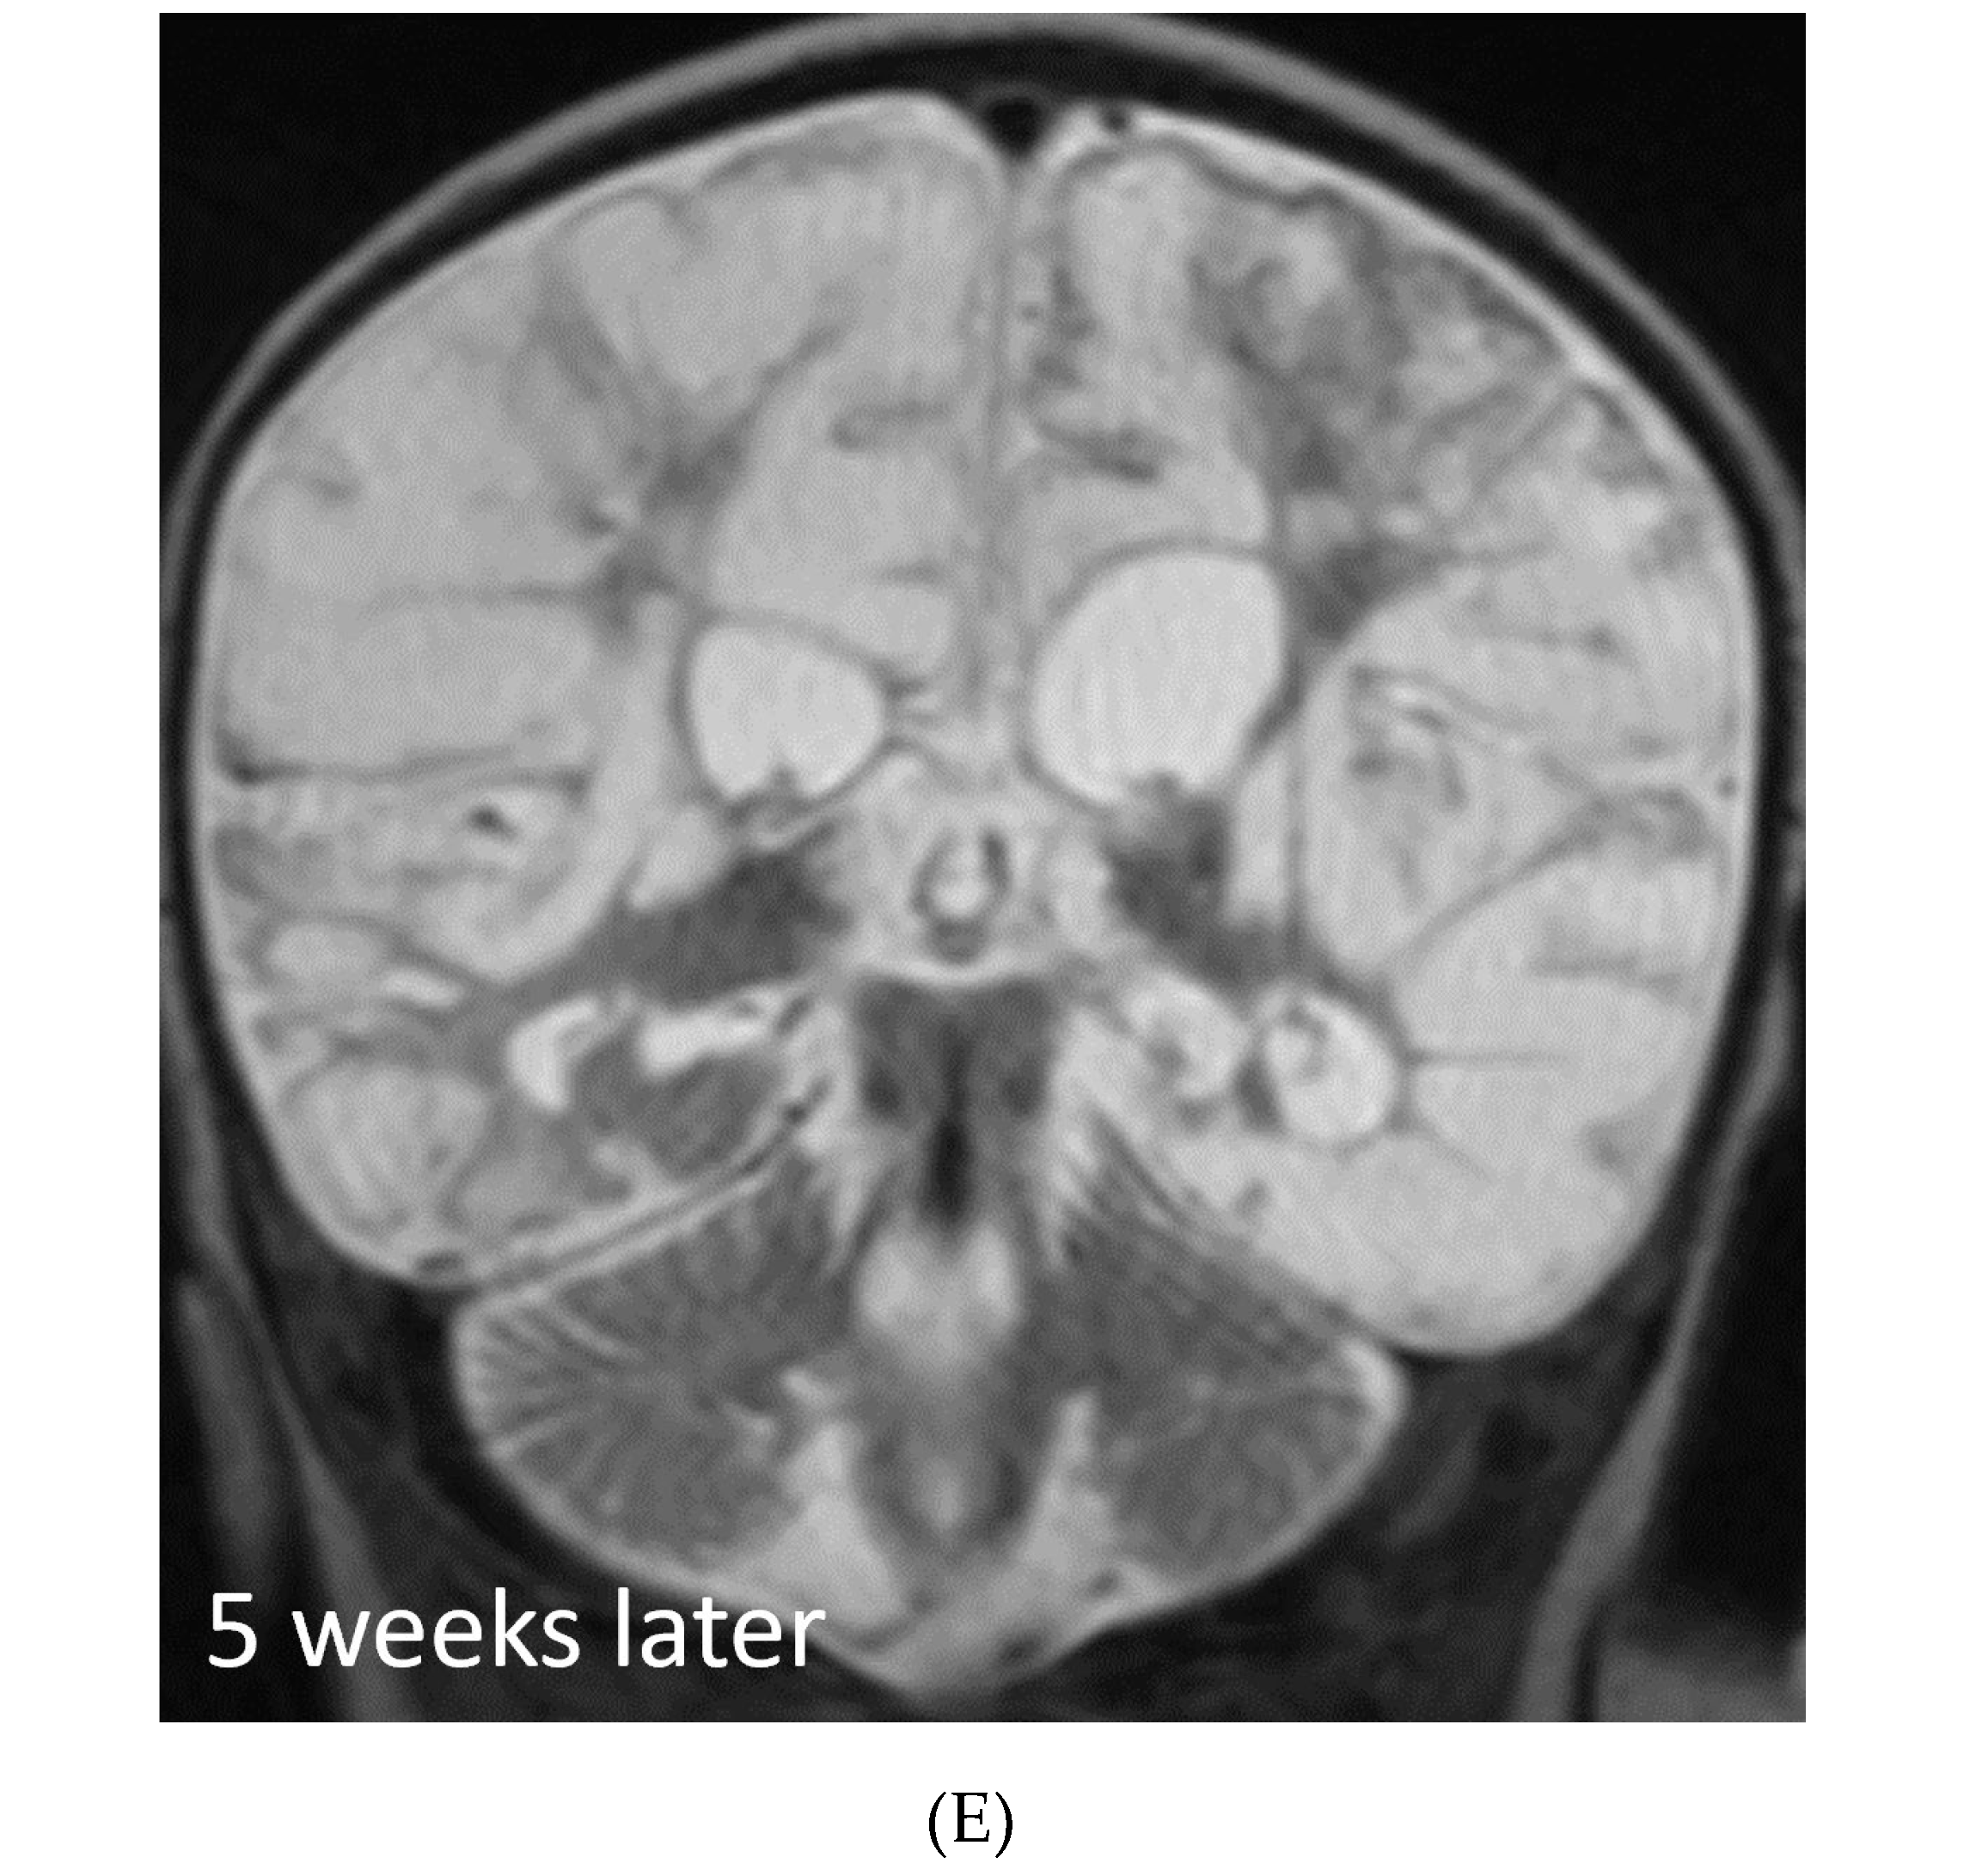

SYSTEMIC MENINGEAL METASTASES (SMM)

MOYA MOYA